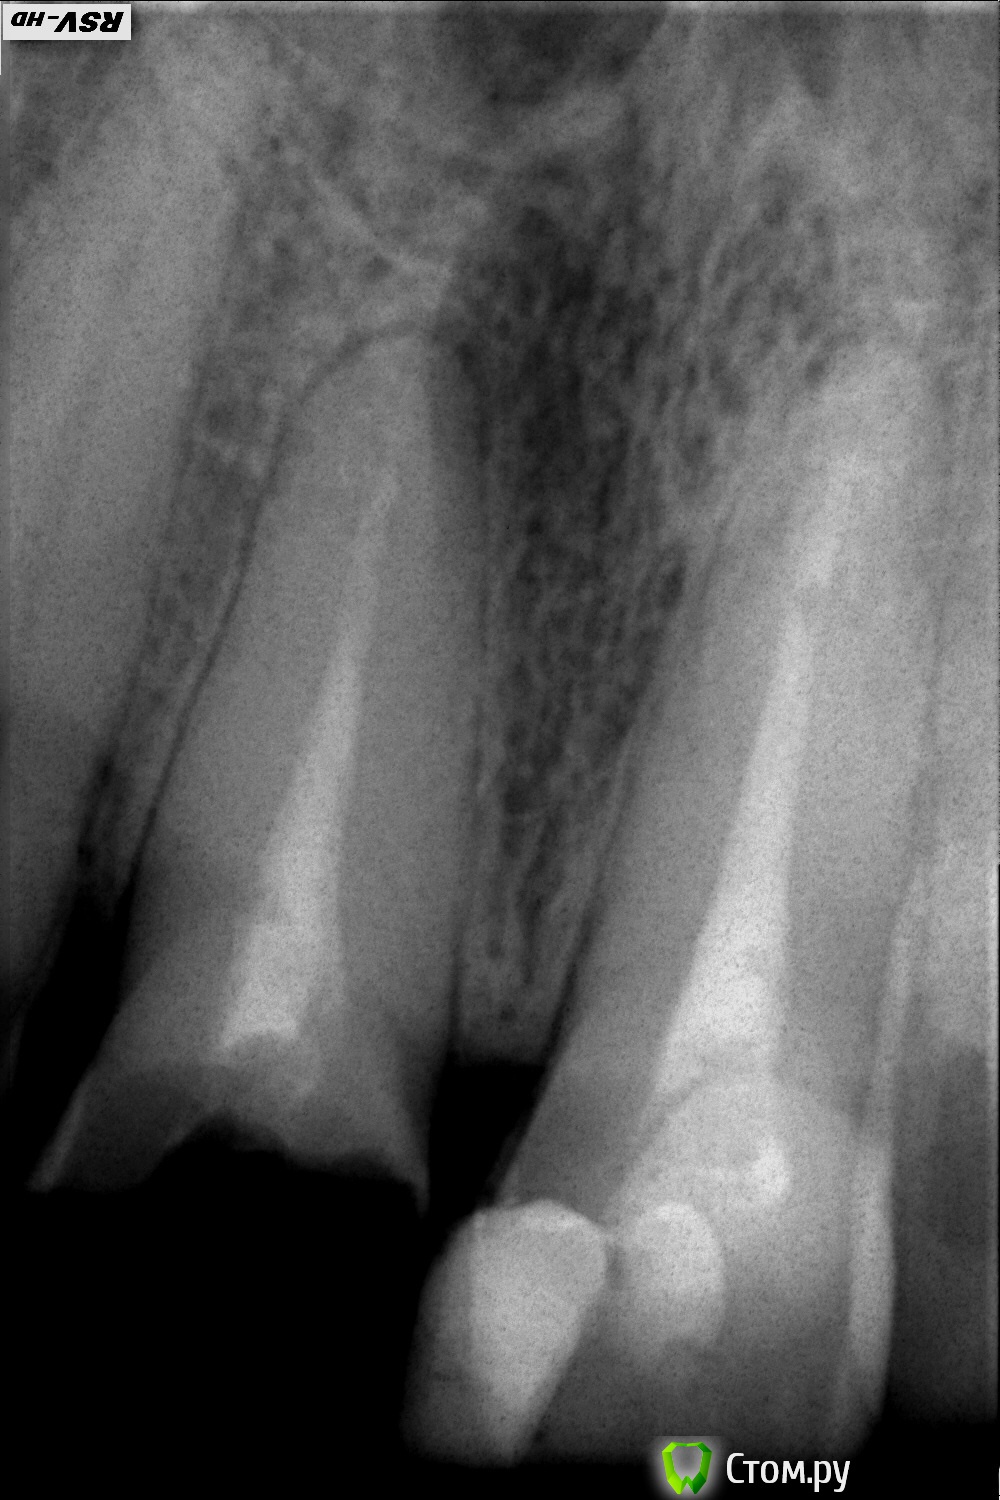

Состояние до лечения на снимках:

снимок 1 –  прицельный,

Снимки показали наличие гранулемы на 11 зубе.